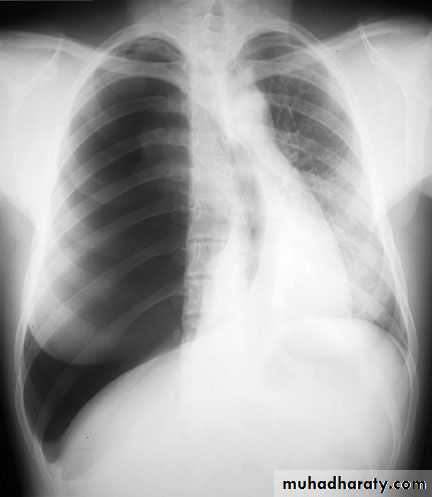

Hemothorax

X-ray hemothorax

X-ray pneumohemothorax